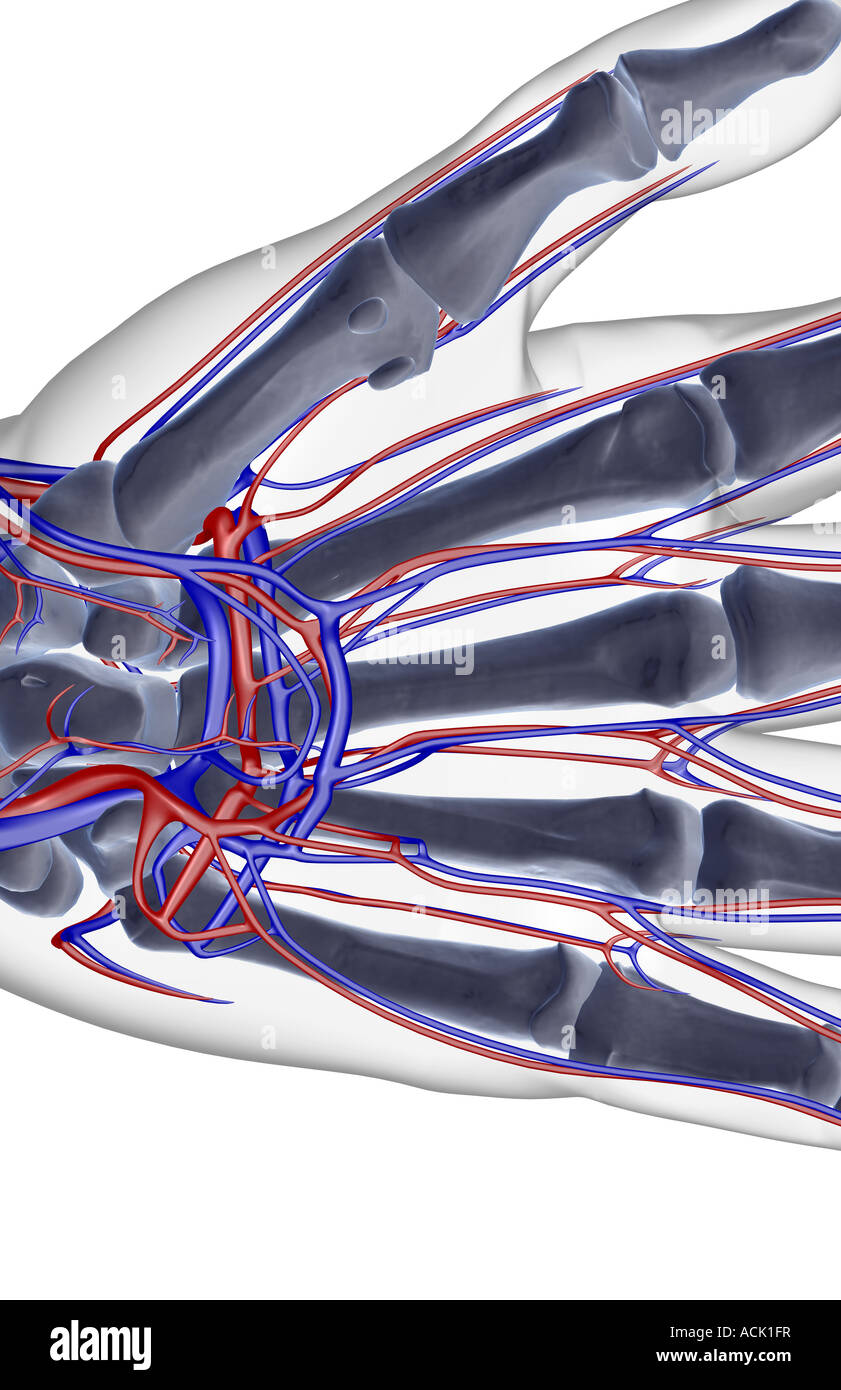

The blood supply of the hand Stock Photohttps://www.alamy.com/image-license-details/?v=1https://www.alamy.com/stock-photo-the-blood-supply-of-the-hand-13174858.html

The blood supply of the hand Stock Photohttps://www.alamy.com/image-license-details/?v=1https://www.alamy.com/stock-photo-the-blood-supply-of-the-hand-13174858.htmlRFACK1FR–The blood supply of the hand